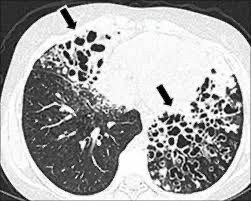

Cyndrical bronchiectasis

regular pattern in the airway wall that is dilated and RIGID. Occurs for 6-10 generations and ends abruptly due to obstruction.

Varicose bronchiectasis

Irregular pattern with areas of constriction and dilation Distorted bulbous shape.